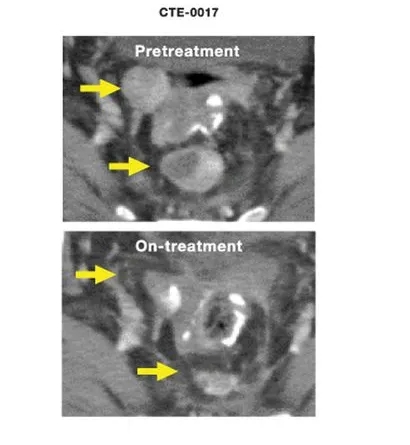

图示经过几周治疗后,患者病情得到明显控制